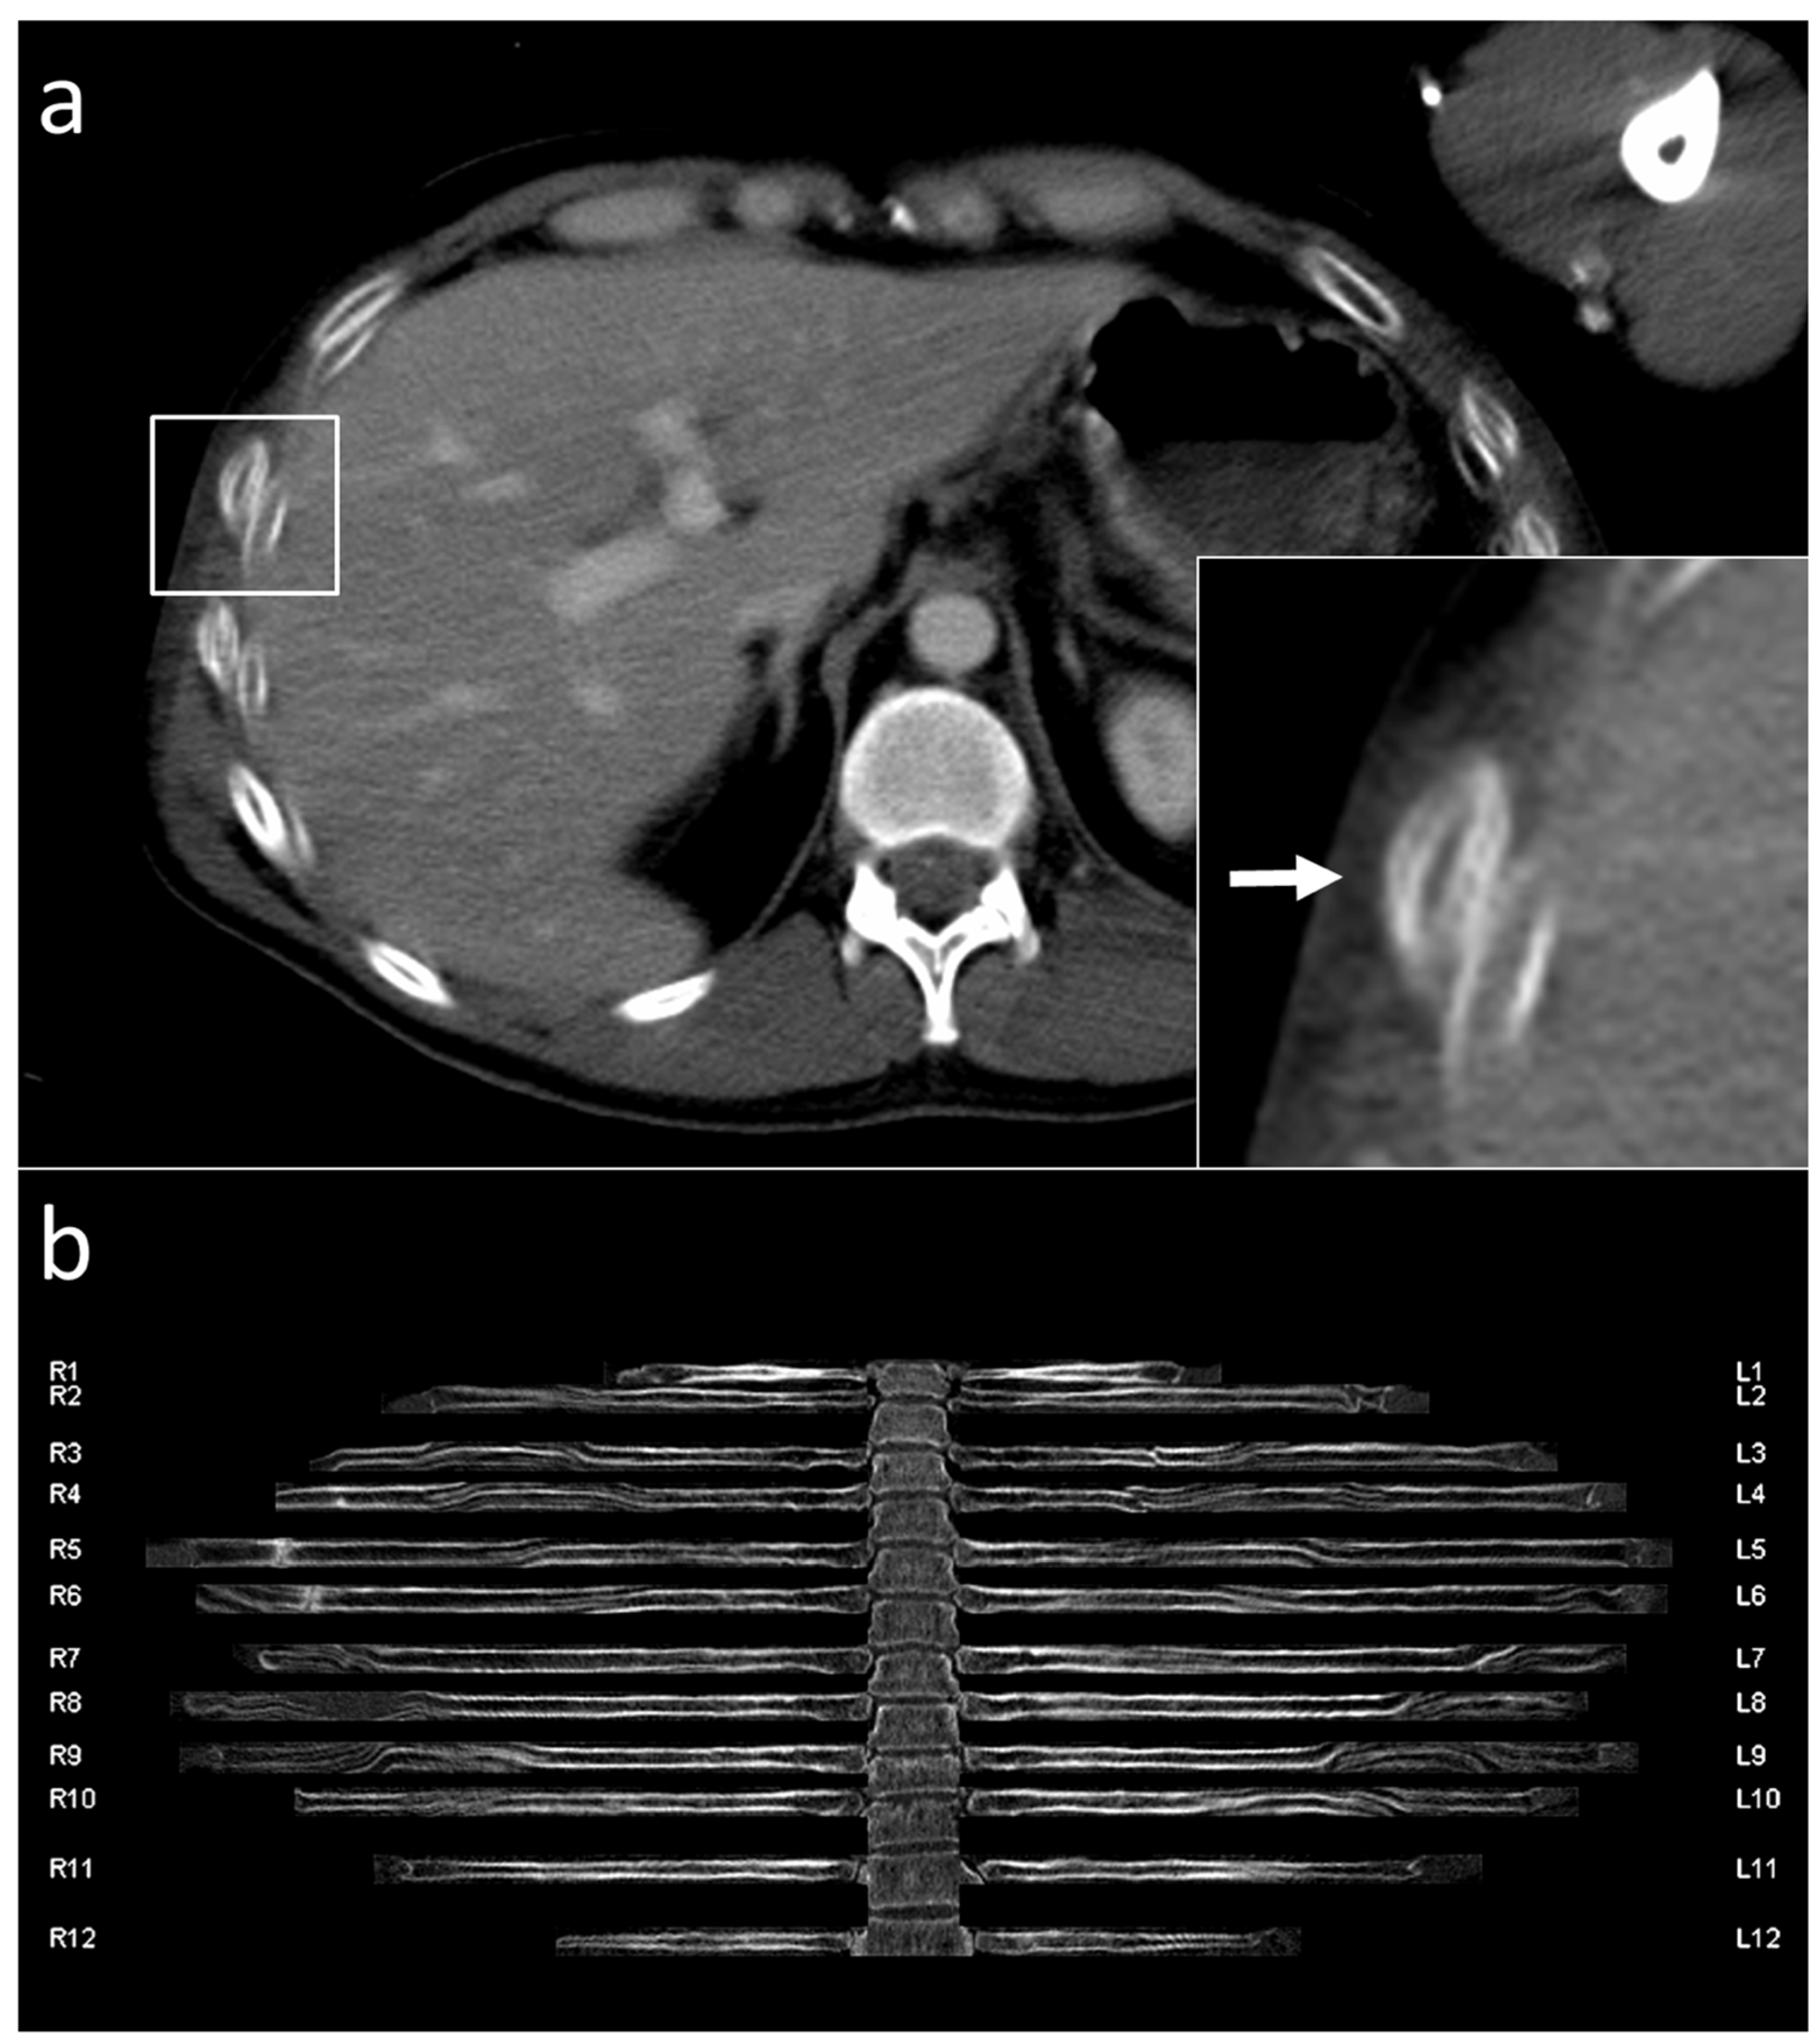

2.2. CT Acquisition and Post-Processing

2.3. Image Analysis